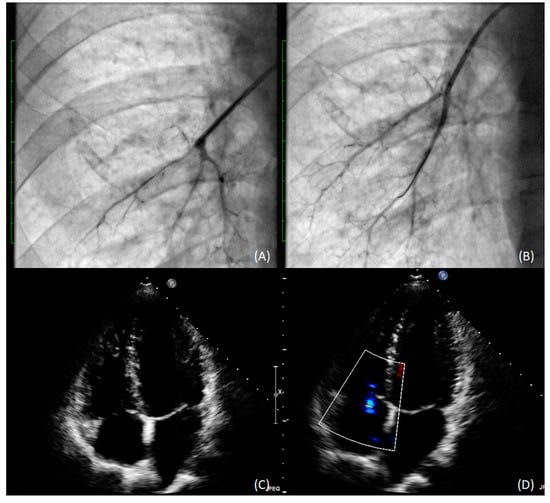

2. Case Presentation